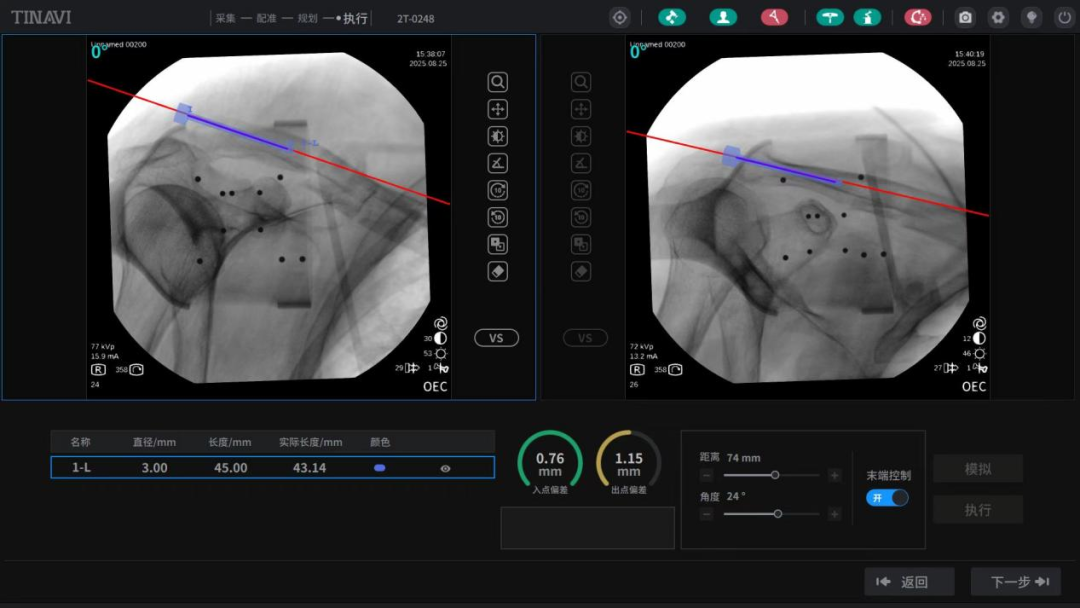

定“路线”:天玑机器人机械臂缓缓移动,精准标记定位点,C臂机快速捕捉影像并上传系统,自动规划出最优进针点和钉道;

做“小切口”:仅在锁骨远端开了个0.5cm的“绿豆”般微小切口,用开路锥钻开骨远端皮质,将3.0mm弹性髓内钉顺行插入锁骨髓腔——第一阶段骨折初步复位固定,顺利完成!

周占锋主任团队将机器人导航的精准优势与人工诊疗的经验智慧完美融合,一次性完成“骨折复位、髓内钉固定”。